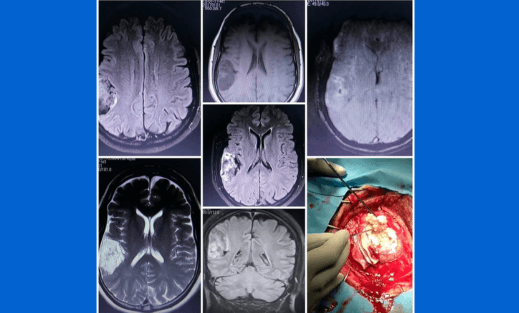

Brain Tumors

Neurosurgeons diagnose and treat both benign and malignant brain tumors. Surgical interventions may involve tumor resection or biopsy to alleviate symptoms and enhance the patient's quality of life.Dr. Amit Aiwale provides comprehensive and cutting-edge Brain Tumors treatment, ensuring personalized care for each patient's unique needs.